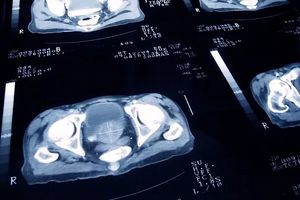

پژوهشگران بریتانیایی در بررسیهای آزمایشی خود به این نتیجه رسیدند که دُزهای پرتودرمانی برای مبتلایان به سرطان پروستات میتواند تا ۷۵ درصد کاهش یابد. به گفته آنها پنج دُز بالاتر … Read More